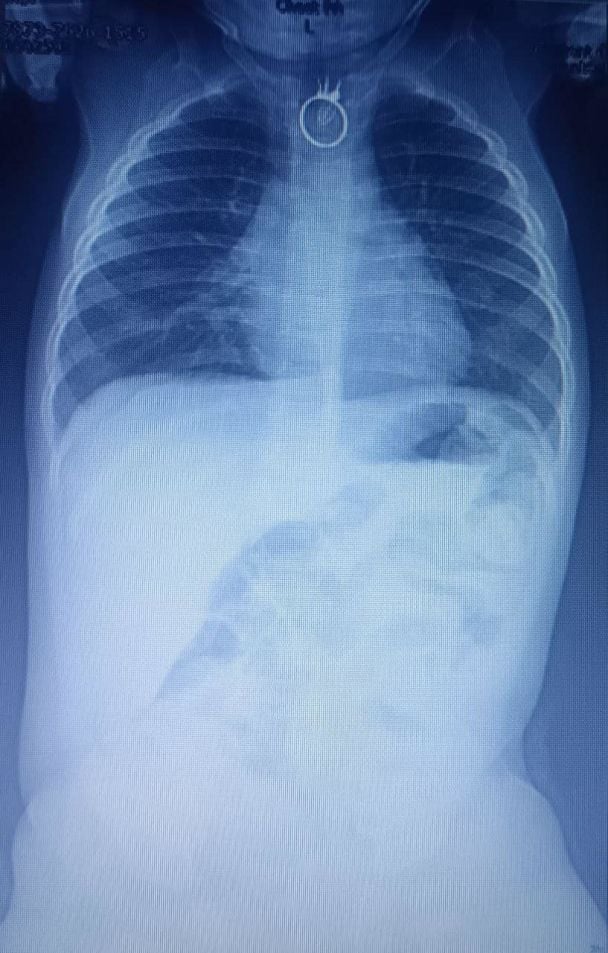

"Тогда они поняли, что, возможно, мальчик проглотил посторонний предмет. После этого родители сразу отправились в местную больницу в Новом Роздоле. Там врачи провели малышу рентген, на котором обнаружили посторонний предмет. Вскоре ребёнка немедленно на машине скорой помощи доставили в Центр детской медицины больницы "Охматдит", - говорится в сообщении.

"Сразу после госпитализации, в два часа ночи, мы взяли ребёнка на операционный стол и провели ригидную эзофагоскопию с удалением постороннего тела. Это было кольцо. Всё прошло успешно и без особенностей. Однако игрушечное кольцо немного повредило пищевод", – рассказал детский хирург Александр Колодий.